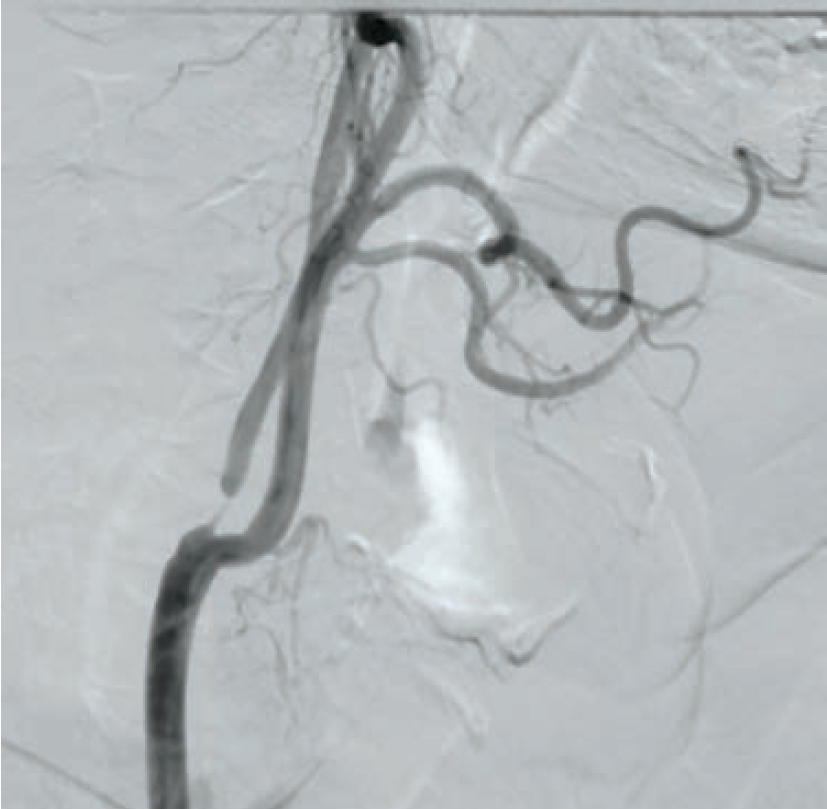

A 70-year-old hypertensive male presented with non-ST elevation myocardial infarction. Electrocardiogram showed ST depression. A complete blood count, complete blood chemistry, and PT/INR were in normal range. Lipid profile showed an LDL level of 147 mg/dl, triglycerides of 260 mg/dl, and HDL of 33 mg/dl. Coronary angiography showed triple-vessel coronary artery disease, sparing the left main stem. The patient was advised to undergo CABG surgery. During the surgical work-up, he was found to have a history of a TIA 3 months prior involving the left side of the body. Carotid Doppler showed a severe 95% ostial stenosis due to mixed plaque in the right internal carotid artery (RICA) and a mild stenosis causing 20% luminal narrowing in the left internal carotid artery. CT brain plain showed no infarction or hemorrhage. A carotid angiography and cerebral DSA showed severe stenosis at the ostium of RICA with no calcification (Figure 1). For the left ICA, both external carotid and vertebral arteries were normal. Cerebral digital subtraction angiography (DSA) showed normal intracranial circulation. A multidisciplinary approach, with a heart team including neurologists, cardiovascular surgeons, and an interventional cardiologist was adopted for this patient during the complete workup. The heart team recommended carotid revascularization prior to surgical coronary revascularization, as the patient was asymptomatic and at an intermediate risk from a coronary viewpoint. After a discussion with the patient and his family about the management options, advantages, and risks, a combined decision for CAS was made, due to its less-invasive nature as compared to CEA.

Following aseptic measures and under local anesthesia, a 7 French (Fr) right femoral access was obtained using a routine-length sheath. An .035-inch J-tip guide wire was then parked at the right common carotid artery (RCCA) using a 5 Fr Judkins right catheter, exchanged by a 7 Fr multipurpose guide. This was followed by advancement of a FilterWire EZ (Boston Scientific) across the ostial internal carotid artery stenosis, and deployed in the distal part of the extracranial ICA (Figure 2). After deployment of the FilterWire EZ, a direct stenting strategy was adopted to minimize thromboembolization. A 6 mm x 40 mm self-expanding stent was deployed at the RICA ostium (Figure 3). To our surprise, the view after stent placement showed zero flow into the distal RICA. (Figure 4) The reason appeared to be choking of the filter due to thromboembolization. The filter appeared to be overwhelmed by the volume of the debris captured. A 6 Fr Export catheter (Medtronic) was employed to suction debris from the distal ICA (Figure 5). We also administered pharmacotherapy using intra-arterial nitrate boluses and a weight-based tirofiban bolus. After these measures, there was fair flow into the distal ICA. During the period of no flow, the patient had transient hemispheric ischemic signs and an oropharyngeal airway was required, but his vitals remained stable. These symptoms rapidly resolved after establishment of ICA flow. After establishing blood flow, the proximal half of the stent that remained under-expanded was post dilated using a 4.5 mm noncompliant balloon at 12 atmospheres (Figure 6). Post dilatation, the angiographic view demonstrated good stent expansion and adequate distal flow (Figure 7). The distal protection device was then successfully removed using its retrieval sheath. The final DSA angiogram revealed excellent flow into the distal carotid (Figure 8A) and intracranial vasculature (Figure 8B), confirming no intracranial embolization. The guide was then safely removed over the .035-inch guide wire.